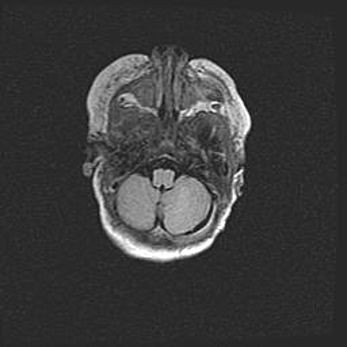

Аномалия Денди-Уокера. Признаки гипоплазии мозолистого тела.

Возраст: 5 месяцев 3 дня

Вес: 5550 г

Пол: мужской

Окружность головы: 39 см

Срок гестации: 40 недель

Аномалия Денди-Уокера – это порок развития головного мозга, для которого характерна триада симптомов: гипотрофия или аплазия червя мозжечка и/или полушарий мозжечка, расширение четвёртого желудочка с формированием ликворной кисты задней черепной ямки, гипертензионная гидроцефалия различной степени.

Гипоплазия мозолистого тела относится к дефектам внутриутробного этапа развития мозговой ткани, возникающим в процессе закладки структур головного мозга, что происходит на начальных этапах развития эмбриона.